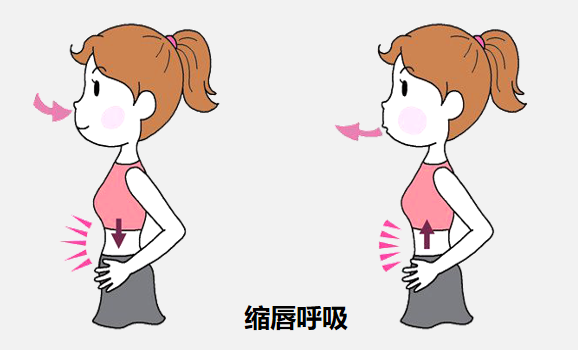

一项随机对照试验评估了(le)认知行为干预联合呼吸功(gōng)能训练在间质(zhì)性肺炎(yán)患者中(zhōng)的(de)应用效果,其中对照组在常(cháng)规护理基础上采用(yòng)呼吸功能(néng)训练,包含腹式呼吸、缩唇(chún)呼吸、阻力呼(hū)吸及(jí)相关呼(hū)吸训练(liàn),结果显(xiǎn)示,该治疗方式有效(xiào)增加了患者呼吸活动及膈肌活动(dòng)能力,使其肺容量增(zēng)加、氧气量更足,疾病症状改善(shàn)更好。

缩(suō)唇呼吸:

取坐位或半坐卧位进行口闭(bì)式(shì)呼吸,鼻子呼吸时缩唇,培养(yǎng)慢呼吸习(xí)惯,3次/d,每次>8 min,增加潮气量(liàng)。